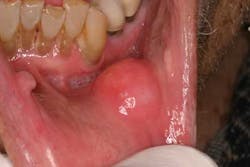

Tongue: Ask the patient to stick out his or her tongue and move it from side to side (figure 2). It should move easily and completely to both sides without spasm or asymmetry. Note any masses, ulceration, or swelling. When there is a nerve paralysis of the hypoglossal nerve, the tongue will usually deviate to the side of the lesion. Observe the dorsum of the tongue, noting any discolorations, irregularities, or limitations to movement, all of which may be a sign of cancer. Notice the circumvallate papillae and lingual tonsils, which are often mistaken for pathologic lesions. One of the most common sites of oral cancer is on the lateral border of the tongue, and it must be evaluated completely. This often requires using gauze to pull the tongue out and roll it from side to side while retracting the cheek with a tongue blade. A dental mirror may be necessary to visualize the base of the tongue (part of the oropharynx). This area is best viewed by pulling the tongue forward while holding it with 2X2 gauze, rolling it up into a position that enables a clearer view. Next, palpate the dorsum and lateral margins of the tongue, paying special attention to any masses or firm/fixated areas. Being careful not to gag the patient, palpate the lingual tonsils. Finally, have the patient touch the roof of the mouth with the tip of his or her tongue. This will allow the examiner to inspect the ventral surface of the tongue.